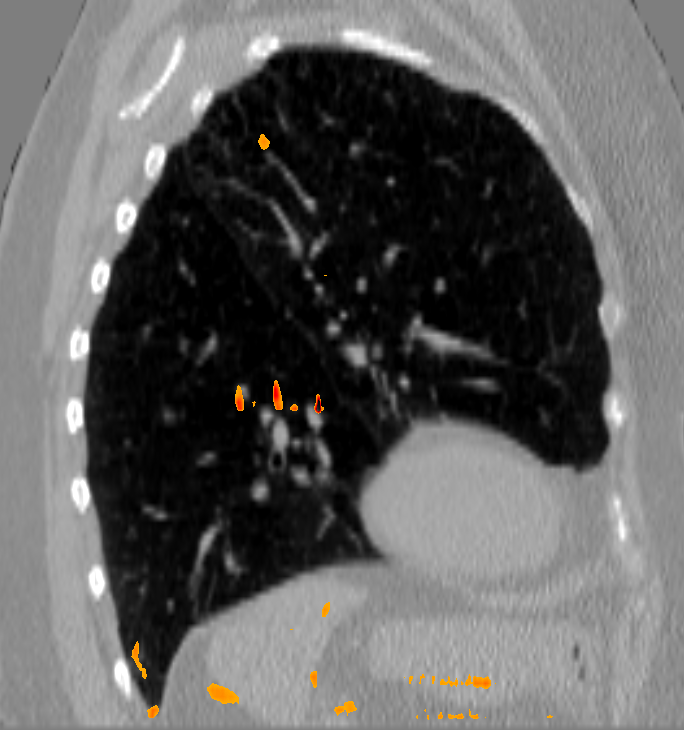

Analysis of the DVF with respect to anatomically implausible deformations showed that the FoF per image dataset was on average 0.25 % of the calculated deformation vectors. The average Jacobi determinant value was 1.00 0.32. A deeper inspection of the Jacobi determinant values revealed that folding occurs mainly in the area of large deformations close to the image or patch border where tissue can move out of or into the field of view.

The initial average landmark distance between consecutive phase images was 2.25 1.55 mm for the Popi datasets and 2.19 2.02 mm for the DirLab datasets. The proposed registration algorithm could decrease the average distance to 1.24 0.90 mm and 1.54 1.31 mm, respectively. For a comparison with existing 4D registration methods we applied the publicly available method by [23] to the respiratory datasets and achieved average registration errors similar to the ones of our method: 1.56 1.42 mm for the DirLab and 1.11 0.87 mm for the Popi datasets. The construction of trajectories for voxels requires the combination of all DVF of a 4D dataset. As a consequence the registration error at the start of a trajectory gets propagated over time and increases or decreases with the combination of the different DVF. In Fig. 4 the error evolution is visualised for the three test datasets. At the beginning the mean registration error is 1.54 mm for the DirLab datasets and 1.24 mm for the Popi datasets. The error then increases to a mean of 2.58 mm for DirLab and 2.07 mm for Popi in the middle of the periodic motion. In the end of the breathing cycle the error falls to an error around 1 mm for both datasets. A similar error propagation pattern could be measured for the Sunnybrook datasets. For the Sunnybrook datasets segmentations are only available for the extreme phases, which allows only four comparisons per dataset. When starting with the end-diastolic phase a comparison in the middle of the cyclic motion to the end-systolic segmentation and in the end of the cycle motion to the original end-diastolic segmentation is possible. The same applies when starting with the end-systolic segmentation. In Fig. 4 the red dots indicate the measured DSC overlap, the red dotted line was fitted to the dots and estimates the DSC overlap for phase images without a segmentation available. Compared to a direct registration of the maximum exhale and inhale phases the registration error increased on average by 0.48 mm with the combination of the DVF. The average registration error for the extreme phases in the Popi dataset increased from 1.46 1.59 mm to 1.98 1.56 mm when we registered the whole 4D dataset instead of the two extreme phases solely. The same analysis reported an increase from 1.83 2.35 mm to 2.54 2.01 mm for the DirLab images and and decrease in the DSC from 0.86 0.10 to 0.79 0.14 for the Sunnybrook data. The DVF of the 4D evaluation showed a FoF of 0.02 % and an average Jacobi determinant of 1.00 0.06.

b) DirLab08 with overlayed image foldings

(Jacobi determinant 0)

b) DirLab08 with overlayed image foldings

(Jacobi determinant 0)